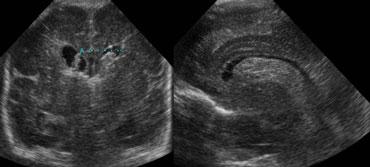

TRÁI: Mặt cắt đứng ngang, mũi tên xanh lá chỉ xuất huyết độ 3. PHẢI: Mặt cắt đứng dọc, mũi tên vàng chỉ nhồi máu tĩnh mạch.

Xuất huyết nội sọ độ 3

Hình bên trái là xuất huyết nội sọ độ 3 lấp đầy não thất bên trái.

Cũng lưu ý vùng tăng âm hình nêm ở phía trên-bên của não thất.

Đây là hình ảnh của một ổ nhồi máu tĩnh mạch nhỏ.

Cùng bệnh nhân như trên.

Hai tuần sau, ổ nhồi máu tĩnh mạch đã tiến triển thành vùng giảm âm với sự hình thành nang.